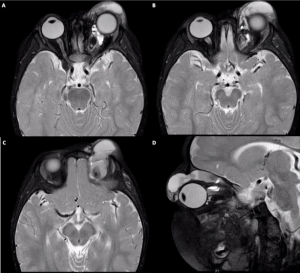

Diagnosis is based on clinical presentation and radiologic findings. CT scan demonstrates cyst-like masses with varying degrees of enhancement along with rim enhancement of cysts with hemorrhage.

On MRI, orbital lymphangiomas are generally isointense on T1-weighted images and hyperintense on T2 images, often with a presence of internal septations within the lesion.[10]

Pathognomonic findings include multiple cysts with air-fluid levels .

Radiology aids in diagnosis of lymphangioma and allows assessment of the size of the lesion and the extent of involvement of surrounding structures. This guides management. For example, depth influences ease of intervention with superficial lesions being easier to treat than deeper ones. A deep, asymptomatic lesion may be observed over a more superficial one, which can potentially be treated with less risk to surrounding structures. Size also influences type of intervention with larger cysts, typically larger than 2cm, being better candidates for sclerotherapy.